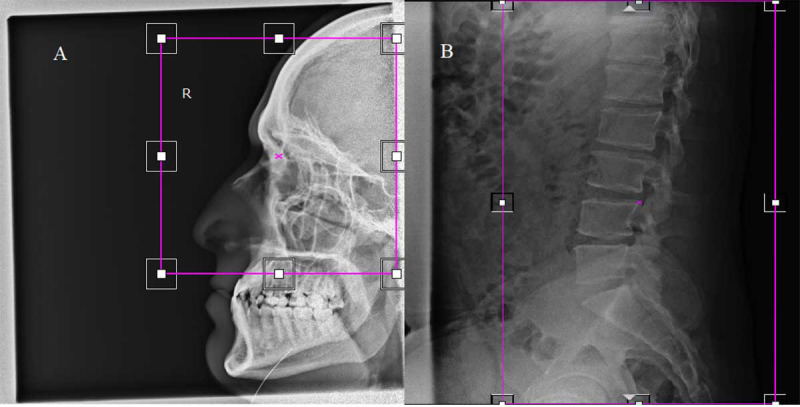

Material and methods: This retrospective analysis was conducted on digital X-ray machine images. Quality control tests were performed to ensure equipment accuracy, and image cropping was then measured by analyzing archived images. Finally, the cropped image fraction and associated unnecessary radiation doses were calculated.

Results: Quality control tests confirmed that all imaging equipment was functioned within acceptable alignment and angle tolerances. The analysis of 911 images revealed a high prevalence of cropping (82%), with significant variation across different projections. Lateral knee images exhibited the highest cropping rate (96.2%), while abdominal images had the lowest (36.1%).